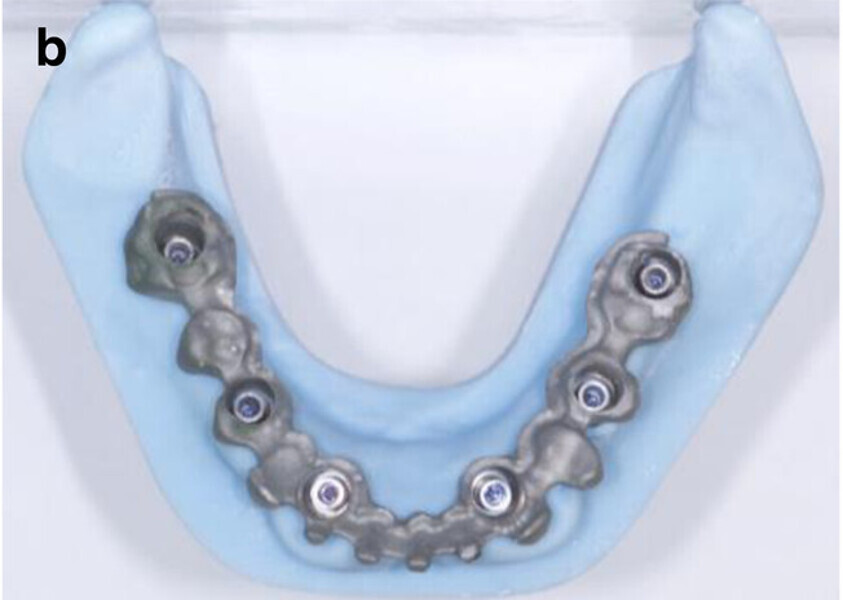

Fig. 7b: CAD/CAM model with the prefabricated titanium abutments (a), CAD/CAM cobalt–chromium framework (b) and composite veneered provisional FDP (c & d) before bonding to the abutments.